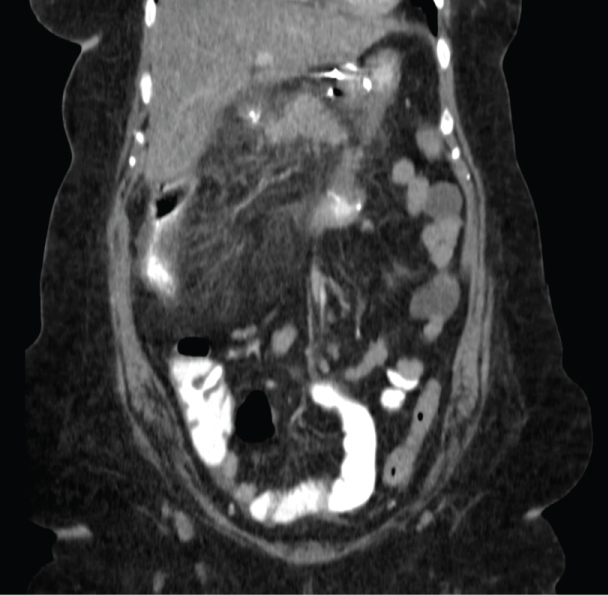

Patient #2 is a 43-year-old woman who underwent Silastic Ring Vertical Gastroplasty (SRVG) for morbid obesity in 1988, with an initial BMI of 62.2 Kg/m². She lost 61 Kg during the first few years following the operation, but since then she gradually gained weight. The patient was referred to our department for a revisional bariatric operation. The preoperative laboratory tests are shown in Table 1. In 2012 she underwent an uneventful laparoscopic BPD and cholecystectomy. Important intraoperative measures are shown in Table 1. The early post-operative period was unremarkable. Some post-operative parameters are also shown in Table 1. Eight weeks after the operation she was admitted to our department because of diffuse abdominal pain, diarrhea, vomiting, and fever up to 39 ℃, and was ultimately diagnosed with colitis extending from the cecum to the sigmoid colon based on a CT scan (Figure 2). Her laboratory tests were as shown in Table 1. As in patient #1, the stool cultures were negative. She was treated with intravenous antibiotics and a clear improvement was observed. One year later, a colonoscopy was performed, demonstrating a normal mucosa throughout the colon, and random biopsies taken from hepatic flexure mucosa were normal. Since that event, she reported no other attacks of abdominal pain, diarrhea, or any other complaints.

Figure 2: CT scan of patient #2, showing colitis extending from the cecum to the sigmoid colon. View Figure 2